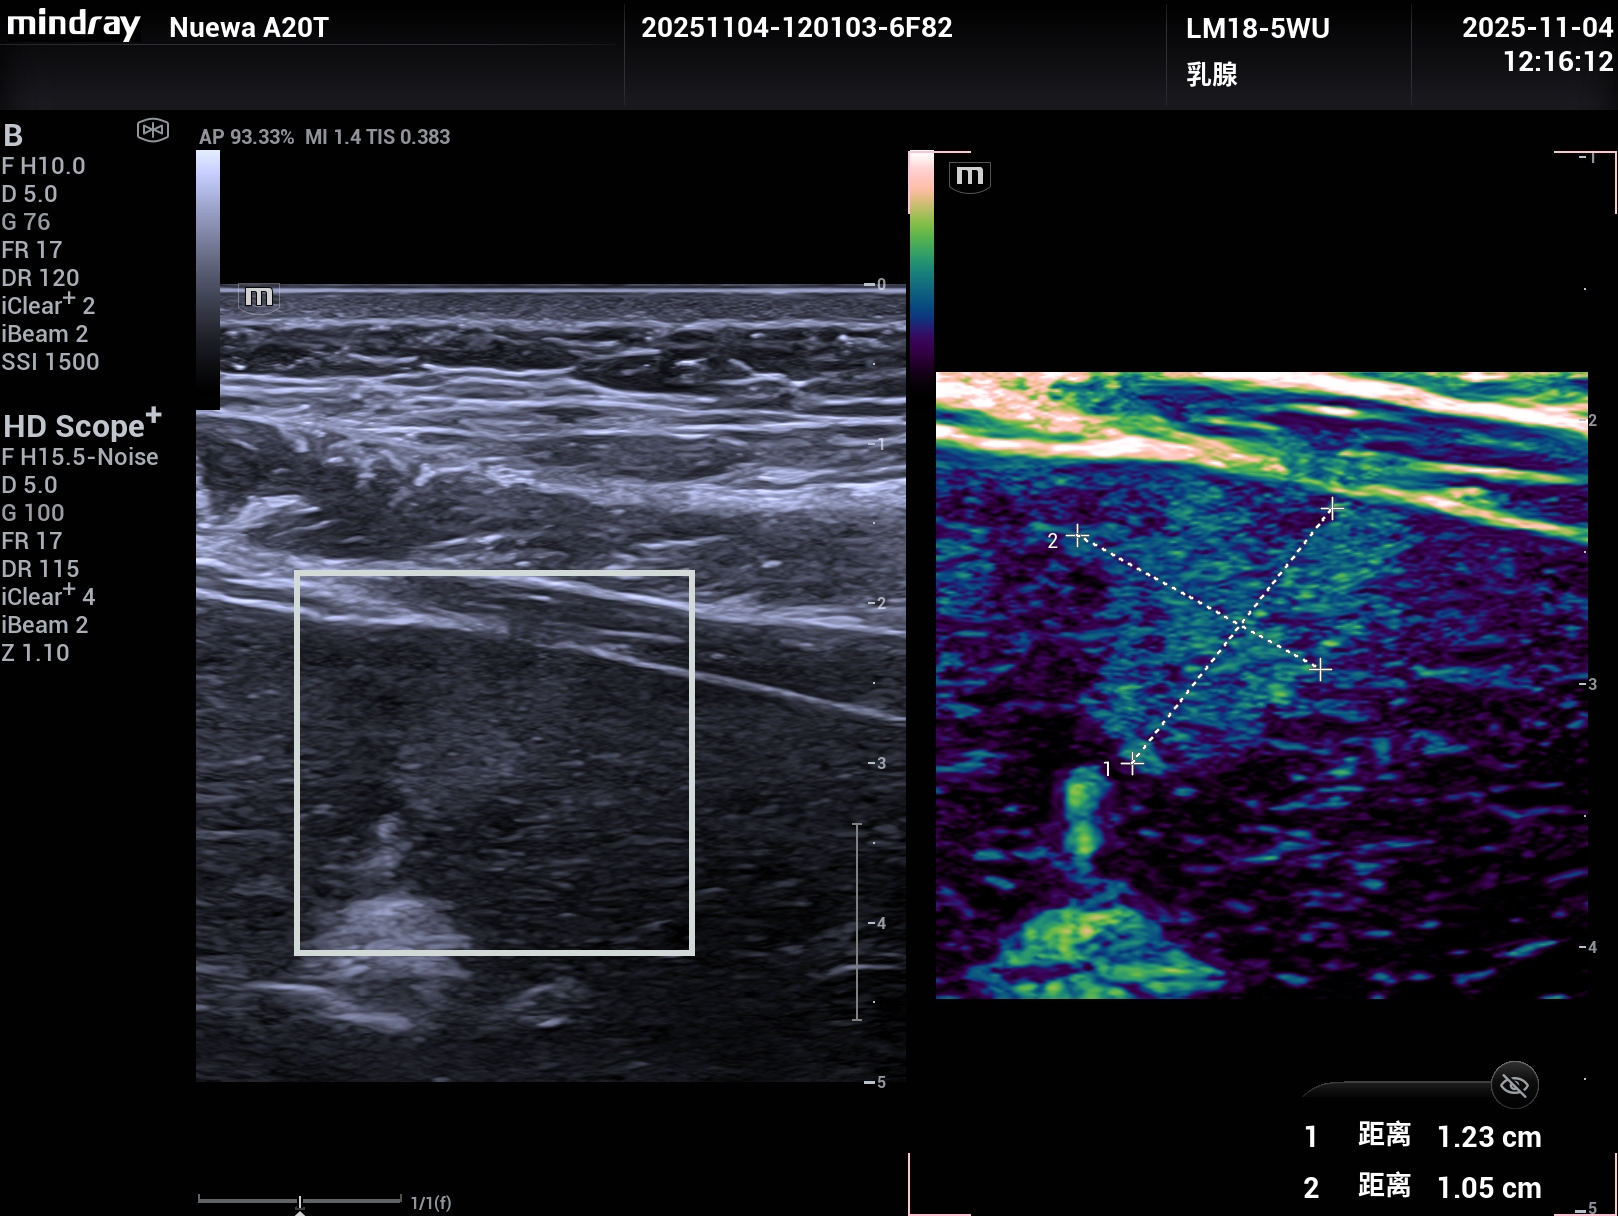

睿瞳技术,是具有独立的发射和接收电路设计的成像技术,组织回声信息更多,图像信息更丰富。

上2幅图是采用了Nuewa A20睿瞳技术的图片,下2幅是没有采用睿瞳技术的图片。